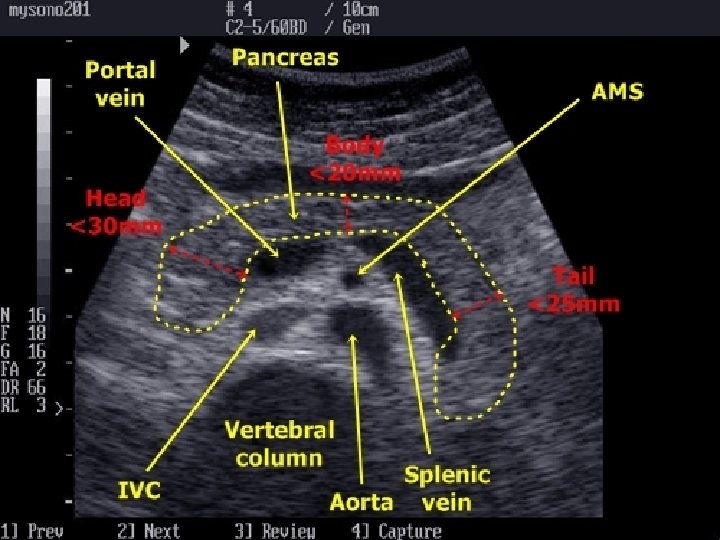

APPEARANCE OF DIFFERENT TISSUES STRUCTURE APPEARANCE Viscera ; Liver Spleen Hypoechoic Muscles Hypoechoic with echogenic lines Blood, Urine, Bile, ascites, water Anechoic Bone, Stone Hyperechoic